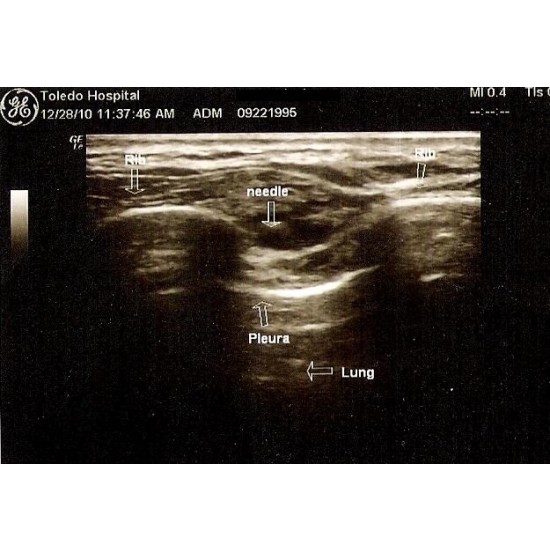

Initial management included over-the-counter NSAIDS, osteopathic manipulation as needed, and physical therapy focused on improving posture, core strength, and neuromuscular retraining, with which she had been non-compliant. Upon her return, conservative care was re-initiated (16 weeks total) with some improvement. The athlete was still unable to compete due to her symptoms, so an intercostal rib block was performed under ultrasound guidance at the single level thought to be the source of most pain. Case Photo #1